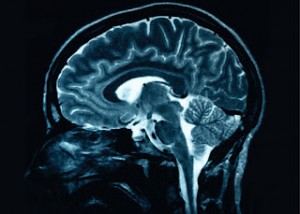

Stress and depression can shrink the brain – Part 1

Major depression, or chronic stress, can cause loss of brain volume, a condition that contributes to the emotional and cognitive impairment.Now a team of researchers, led by scientists at Yale, has discovered a genetic switch that

triggers the loss of brain connections in humans and in animal models of depression.

Research shows that the genetic switch, known as a transcription factor, represses the expression of multiple genes required for the formation of synaptic connections between brain cells, which in turn may contribute to cerebral mass loss in the

prefrontal cortex .

"We wanted to test the idea that stress causes a loss of synapses in the human brain," says lead author, Ronald Duman, professor of psychiatry, neurobiology and pharmacology at Yale.Thus, the researcher continued, "we have shown

that the circuits normally involved in emotion and cognition, are interrupted when this transcription factor is activated".